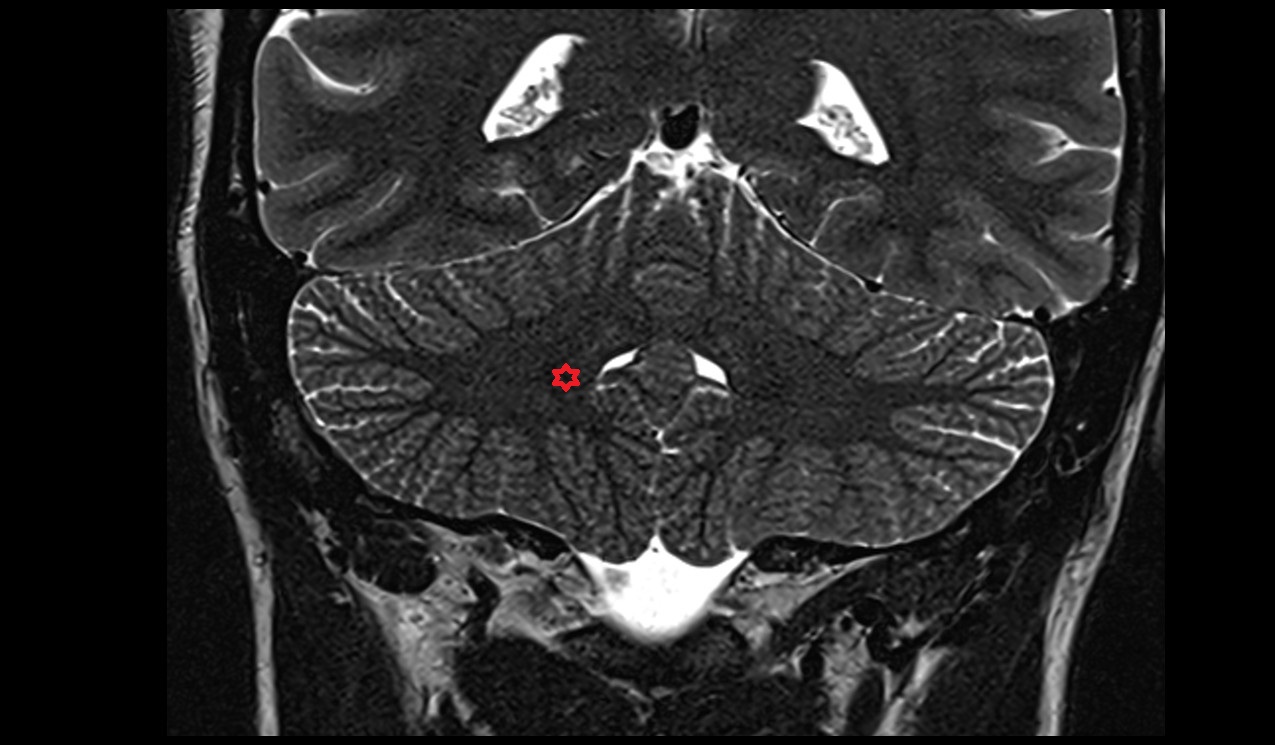

- Cerebellum

- Crus I of ansiform lobule of cerebellum

- Crus II of ansiform lobule of cerebellum

- Paramedian lobule (HVII) of cerebellum

- Simple lobule (HVI) of cerebellum

- Anterior quadrangular lobule (HV) of cerebellum

- Anterior quadrangular lobule (HlV) of cerebellum

- Biventral lobule (HVIII) of cerebellum

- Cerebellar tonsil (H IX)